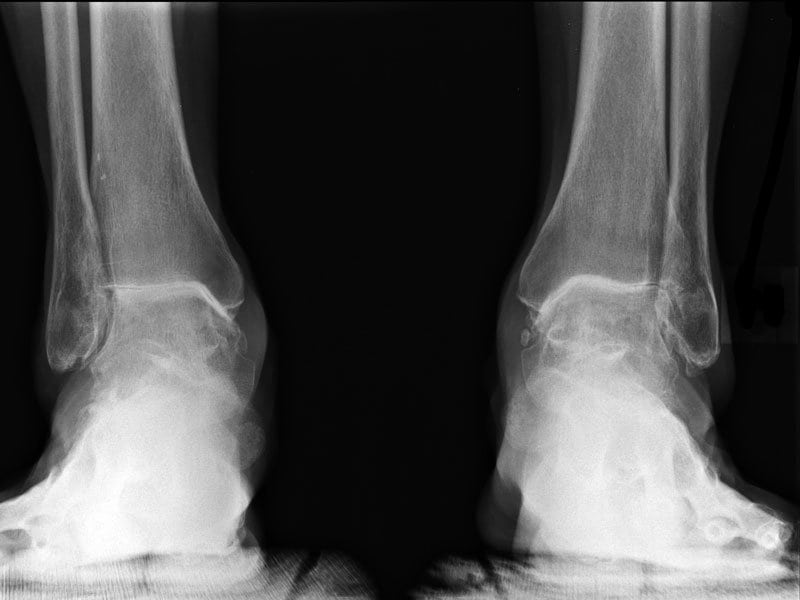

| Подошвенный фасциит | На МРТ врачи выявляют утолщение плантарной фасции и выраженный отек мягких тканей. На поздних стадиях у больных появляется пяточная шпора. Она представляет собой клювовидный нарост на подошвенной поверхности пяточной кости. Шпору можно обнаружить с помощью рентгенографии |

| Плоскостопие и вальгусная деформация стопы | Заболевания можно диагностировать с помощью обычной рентгенографии. МРТ делают лишь в ходе подготовки к их хирургическому лечению |